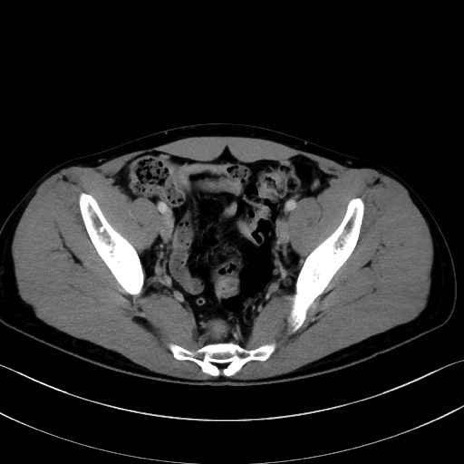

2. 腸腰筋群と骨盤底筋

大腰筋 (Psoas major)

腸骨筋 (Iliacus)

梨状筋 (Piriformis)

内閉鎖筋 (Obturator internus)